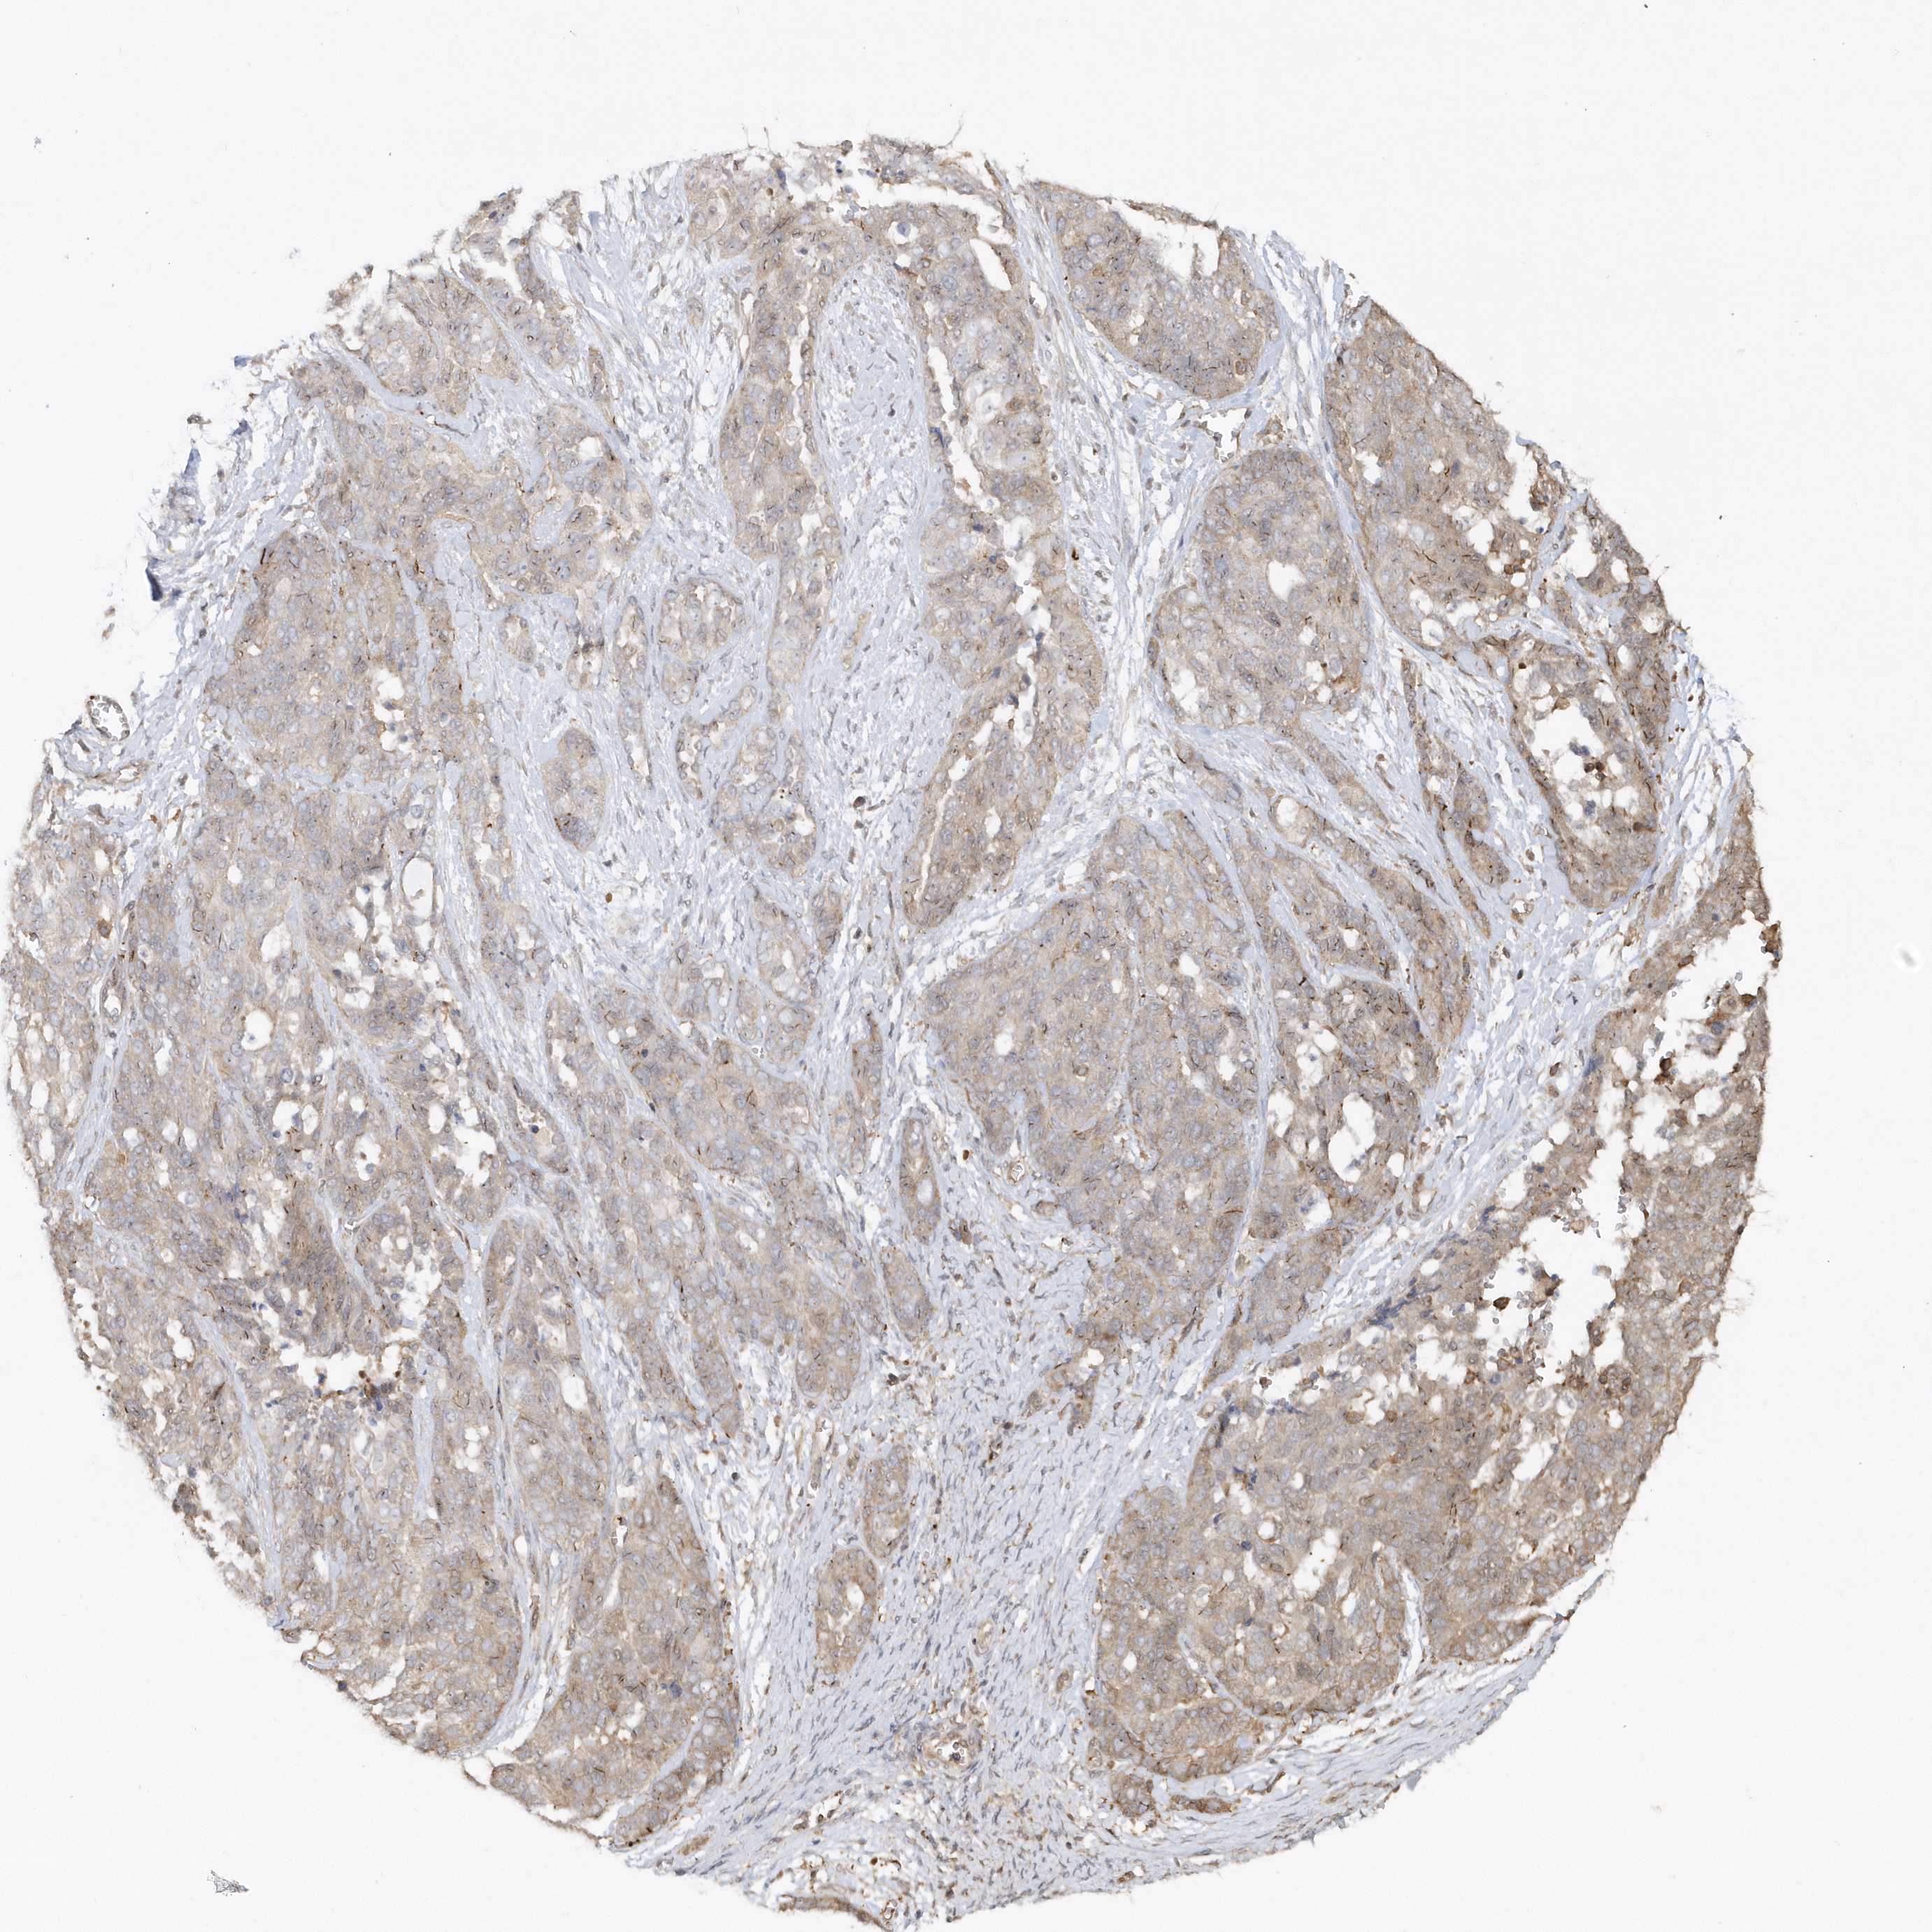

OVARIAN CANCER - Protein expressioni

A mouse-over function shows sample information and annotation data. Click on an image to view it in a full screen mode. Samples can be filtered based on level of antibody staining by selecting one or several of the following categories: high, medium, low and not detected. The assay and annotation is described here.

Note that samples used for immunohistochemistry by the Human Protein Atlas do not correspond to samples in the TCGA dataset.

Antibody stainingi

Antibody staining in the annotated cell types in the current human tissue is reported as not detected, low, medium, or high, based on conventional immunohistochemistry profiling in selected tissues. This score is based on the combination of the staining intensity and fraction of stained cells.

Each image is clickable and will lead to virtual microscopy that enables deeper exploration of all samples and also displays staining intensity scores, fraction scores and subcellular localization as well as patient and tissue information for each sample.

Antibody HPA034757

Cystadenocarcinoma, serous, NOS

Carcinoma, endometroid

Cystadenocarcinoma, mucinous, NOS

Carcinoma, NOS